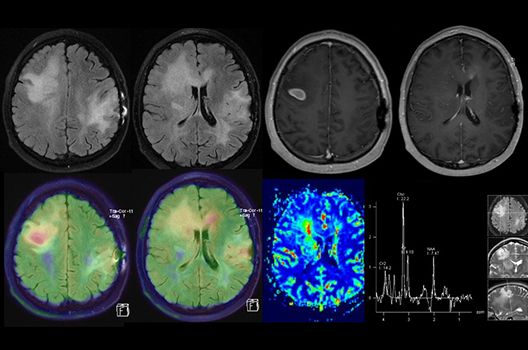

Die Hybridbildgebung mittels PET/MRT spielt insbesondere in der onkologischen Bildgebung eine wichtige Rolle. Eine mögliche Fragestellung ist die Unterscheidung zwischen einem Tumorrezidiv oder therapeutisch assoziierten Veränderungen insbesondere dann, wenn diese Frage mittels MRT alleine nicht beantwortet werden kann.

Die bildgebende Diagnostik und Verlaufsbeurteilung von Tumoren des Nervensystems ist einer der klinischen und Forschungsschwerpunkte unserer Abteilung. Eine besondere Bedeutung kommt der Hybrid-Bildgebung zu. Das Universitätsklinikum verfügt über einen integrierten Ganzkörper-PET/MRT-Scanner, der die Vorteile der MRT-Bildgebung und der Positronenemissionstherapie (PET) vereinigt. Aufgrund der langjährigen klinischen Arbeit und Forschungstätigkeit mit diesem Gerät hat die Neuroradiologie Tübingen maßgeblich zur Etablierung dieses Verfahrens beigetragen. Auch weiterhin forschen wir intensiv an neuen Methoden zur frühen Einordnung von Tumoren und insbesondere Tumorrezidiven, die mit anderen Methoden häufig nicht erfasst werden können.